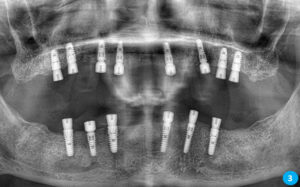

İlk aşamada implant çene kemiğine yerleştirilir. Ardından ortalama 3 ay kadar kişiden kişiye değişiklik gösteren bekleme süreci olur. Bekleme sürecinin amacı kemik oluşumu ve implantın çene kemiğine kaynaşmasını sağlamaktır. Bu süreç bittikten sonra implantın üst yapısının yapılması ise 1-2 haftalık bir zamanda bitmektedir.

Diş çürüğü, diş eti hastalığı, dental travma, diş çekimi, dişlerin sallanması gibi sebeplerle kaybedilen dişlerin yerine kuron-köprü uygulamalarıyla bu eksiklikler tamamlanabilmektedir. köprü uygulaması için kişinin en az sağlam iki dişinin kesilip boyutsal olarak küçültülmesi gerekmektedir ve bu uygulamanın geri dönüşü yoktur. İmplant ise sağlam dişlere dokunulmadan sadece diş boşluğu kullanılarak uygulanan bir tedavidir.

Alt-üst damakta hiç dişi olmayan hastalar hareketli proteze alışamamakta, bulantı reflefsi oluşturmakta ve çoğu hastada damaklar ağızda sıkı bir şekilde durmamaktadır. Bu durum hastaları sosyal yönden olumsuz etkilyebilmektedir. Hiç dişi olmayan hastalara implant önemli bir çözüm oluşturmaktadır.